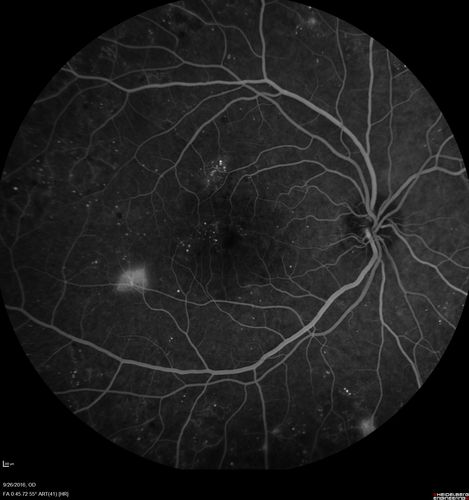

PDR NVD left eye and NVE right eye

41 year old diabetic woman with PDR in both eyes. High risk in the left eye. She had PRP, Avastin, and vitrectomy x 2 in the left eye with final vision of 20/25. The right eye had eventually PRP laser

Proliferative Diabetic Retinopathy NVD left eye and NVE right eye - Ultrawide field FA